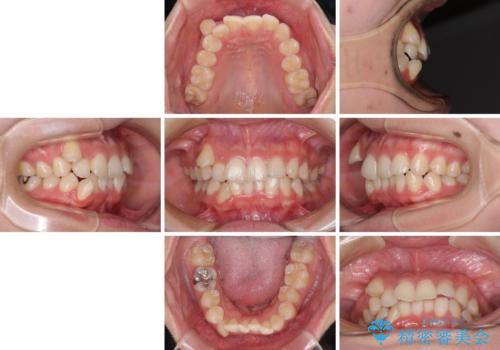

八重歯の抜歯矯正 補助装置とワイヤーを併用したインビザライン矯正治療

- 八重歯と上顎正中のズレを気にして来院された患者様です。

インビザラインによる矯正治療を希望されたため、八重歯改善のための抜歯矯正部分や上顎正中の大幅に位置移動は、補助装置やワイヤー矯正を併用し、その後はインビザラインにて行うこととしました。